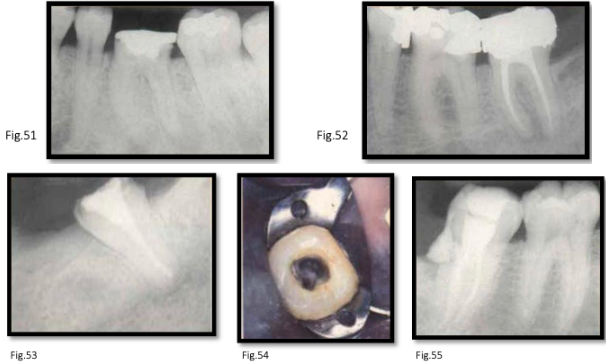

canal anatomy of mn 2nd molar

similar to first molar

distal root: lower incidence of two canals

roots: tend to be closer together [fig. 51-52]

mesial root: usually 2 canals, occasionally 1 (broad bucco-lingually)

rare variations:

single root with single canal [fig. 53]

c-shaped canals → distal canal extends mesially, sometimes including mesiobuccal and mesiolingual canals [fig. 44-45]

difficult to detect on preoperative radiographs